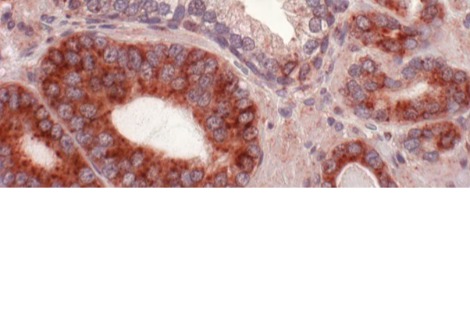

أظهر المختبر أن خمسة خيوط من microRNA تنظم إنتاج هذا الهرمون - والتي توجد في الكروموسوم 21 - معطلة. هذا الكروموسوم الزائد يؤدي بعد ذلك إلى تشوهات في الخلايا العصبية التي تفرز GnRH. تم تأكيد هذه النتائج على المستويين الجيني والخلوي. تمكن علماء Inserm من إثبات أن النواقص المعرفية والشمية التي لوحظت في الفئران كانت مرتبطة ارتباطًا وثيقًا بإفراز GnRH المختل وظيفيًا.

في ضوء ذلك ، قام فريق مختبر Lille Neuroscience & Cognition تحت إشراف Vincent Prévot ، مدير أبحاث Inserm ، بالتحقيق في الآلية التي تنظم GnRH في نماذج الفئران لمتلازمة داون.